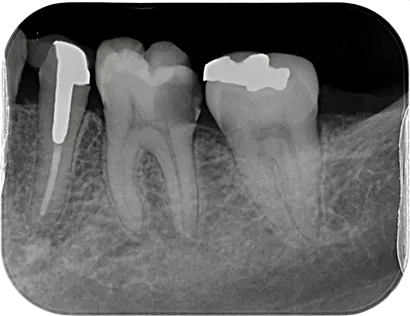

虫歯など様々な理由で歯の内部に細菌感染が広がることがあります。歯内療法(根管治療)とは、文字通り歯の内部の治療で、感染が広がった根管(神経が通る管)に対して適切な治療を行うことにより歯の機能を回復させることができます。

経験と技術が必要とされる

「歯の根の精緻な治療」により、

長期的な口腔内の健康維持を目指します。